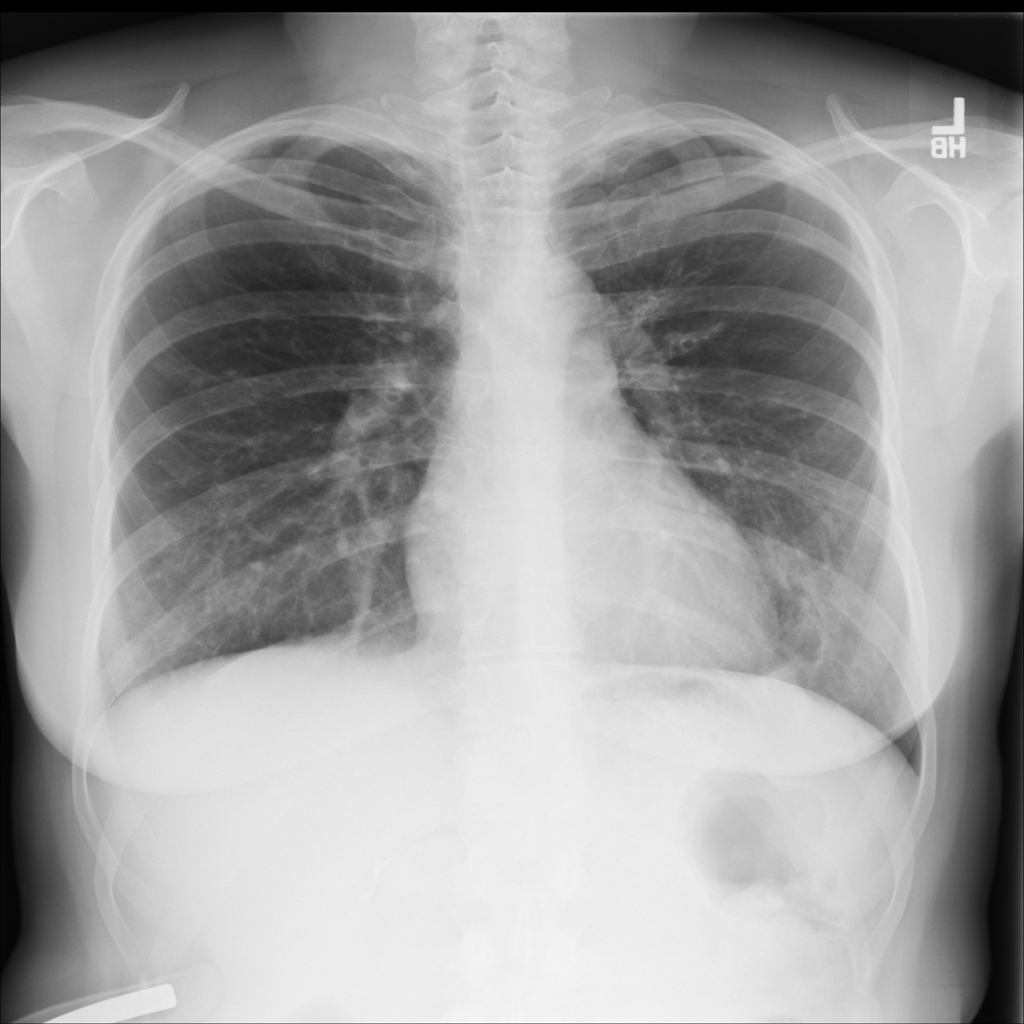

PAT-E960 · IMG-002Fibrosis

PAT-E960 · IMG-002

PA